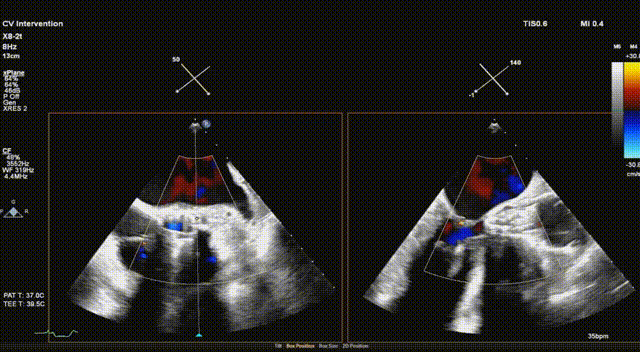

术后超声评估,未见瓣周漏,平均跨瓣压15 mmHg,血流速度197 cm/s